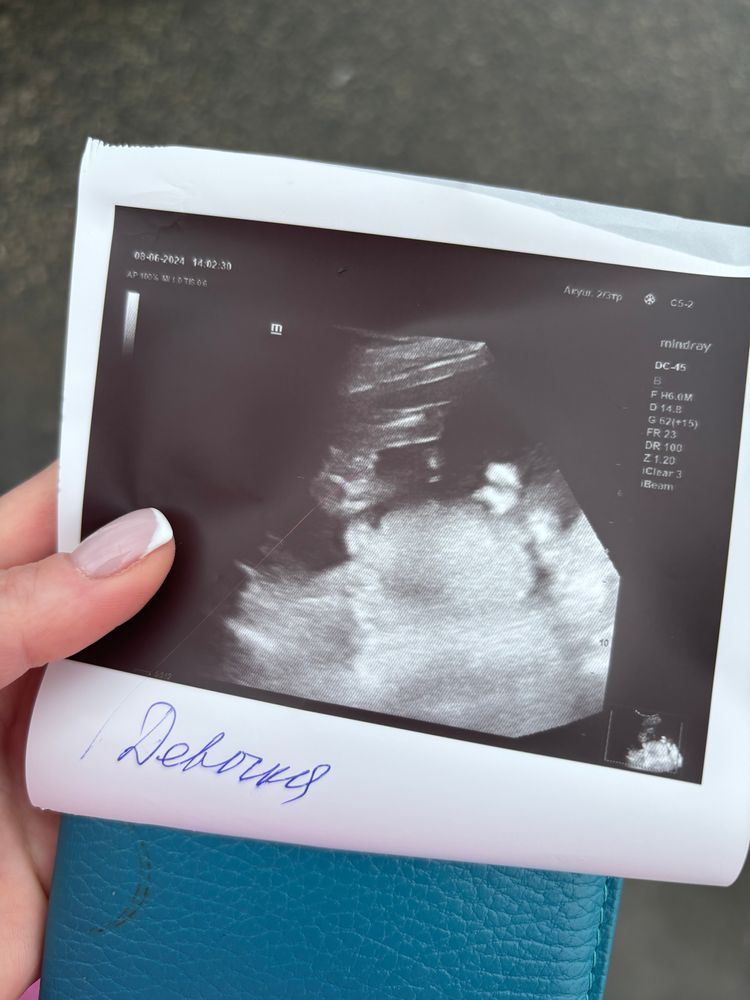

08.06.2024

Натали, в том то и дело, один узист говорит мальчик, другой что девочка, узи вот только щас сделала Вчера на узи сказали мальчик, на этом узи даже подписали что девочка Я не пойму ничего 😂😅

Виктория Букреева, на УЗИ с девочкой, показывали "кофейное зернышко" фото к сожалению нет, но что-то похожее на ваш снимок) с мальчиками вроде очевидные писюли были